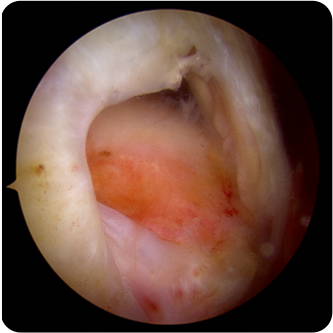

회전근개파열의 여러 모습들

회전근개파열의

어깨의 회전근개파열은 통증이 심했다가도 좋아지거나, 처음부터 통증이 없을 수도 있기 때문에 많은사람들이 방치를 하는 경우가 많습니다.

회전근개가 완전히 파열되었고 오랜시간이 경과한 경우에는 끊어진 힘줄이 말려 들어가서 봉합이 불가능하거나

어깨 전체의 근육 위축을 유발할수있습니다.